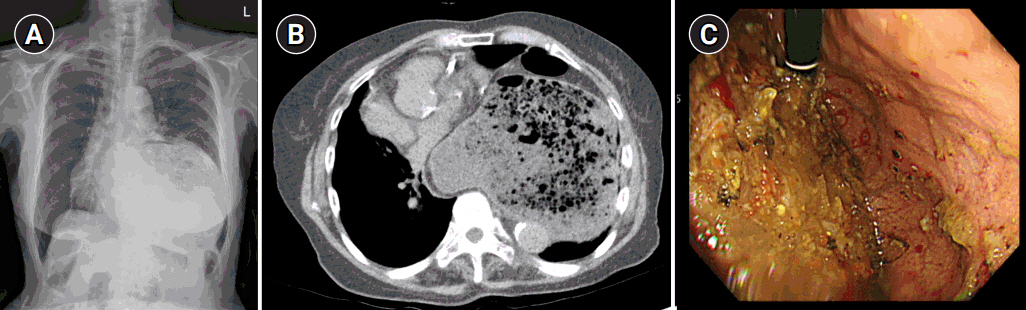

Preoperative chest radiography and computed tomography (CT) confirmed a very large left-sided diaphragmatic hernia, approximately 5.5 cm in diameter, of the stomach and transverse colon (Fig. 1A, B). Esophagogastroduodenoscopy (EGD) showed an abnormal stomach body shape with large amount of food contents, making further evaluation difficult (Fig. 1C). After discussing the results and risk with the patient and her family, the patient agreed to proceed with surgical reduction.

Fig. 1.Preoperative imaging evaluation. (A) Chest radiography showing a left-sided diaphragmatic hernia, (B) abdominal computed tomography showing a diaphragmatic hernia measuring approximately 5.5 cm in diameter. (C) Esophagogastroduodenoscopy showing a large amount of food contents due to gastric outlet obstruction.